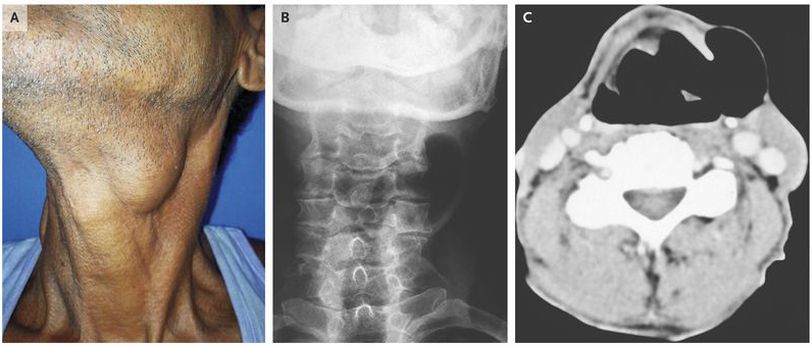

A 58-year-old man presented to the otorhinolaryngology outpatient clinic with a 2-year history of progressive hoarseness and swelling on the left side of his neck. He had no associated dysphagia, regurgitation of food, or dyspnea. He worked as a farmer and had no history of tobacco use. On physical examination, he had nontender, compressible swelling in the left cervical region that transmitted light on transillumination (Panel A). The swelling was accentuated when the Valsalva maneuver was performed Examination with a flexible fiberoptic laryngoscope showed a bulge over the left false vocal cord that was partially obstructing the airway lumen . A diagnosis of laryngocele was confirmed by radiography of the neck (Panel B) and by computed tomography (Panel C), both of which showed a well-defined lobulated structure located in the left paralaryngeal space and extending through the thyrohyoid membrane. A laryngocele is a dilatation of the laryngeal saccule within the sinus of Morgagni, the space between false and true vocal cords. It can result from activity that increases intralaryngeal pressure, such as excessive coughing, straining, playing a wind instrument, or glass blowing. The patient underwent a complete excision of the laryngocele. He remained asymptomatic at a follow-up visit 8 months later.